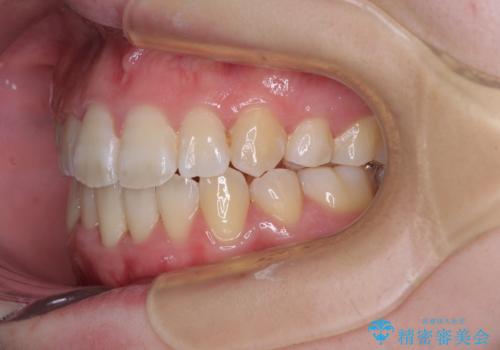

上下非接触で突出した前歯 ワイヤー装置による抜歯矯正

- 上下前歯の隙間と口元の出っ張った感じを気にして来院された患者様です。

上下の隙間は舌突出癖によるもので、またその癖により前歯が前方に出ている状態でした。

口元の出っ張りを改善するため、上下左右第一小臼歯4本を抜去し、ワイヤー装置にて矯正治療を行うこととしました。

舌の突出癖を改善するためのトレーニングをしっかりと行っていただいたことで、比較的スムーズに治療を進めることができました。

口元の突出感もしっかりと改善することができました。